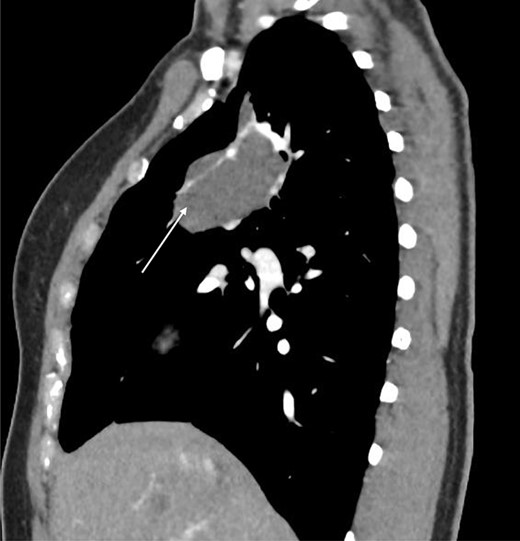

Sagittal CT scan demonstrating pulmonary sequestration in the right upper lung lobe (arrow).